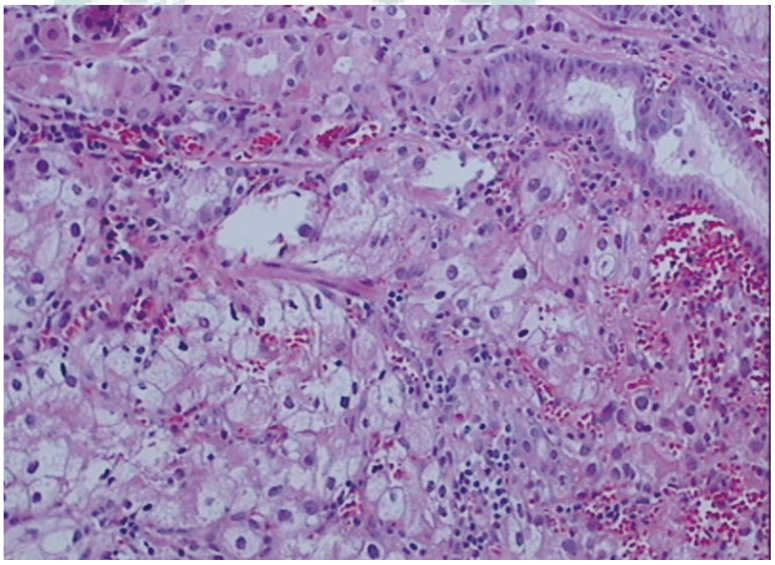

肾透明细胞癌是成人肾脏最常见的恶性肿瘤。常见转移部位为肺脏、肝脏、骨骼、肾上腺、对侧肾脏等,转移至胃部相对罕见,准确的病理诊断和鉴别诊断对于此病的治疗及预后非常重要。现报道右肾透明细胞癌切除术后,以胃部为首发转移并相继出现肺脏、颅骨、肝脏及脑多发性转移且长期生存的患者1例。